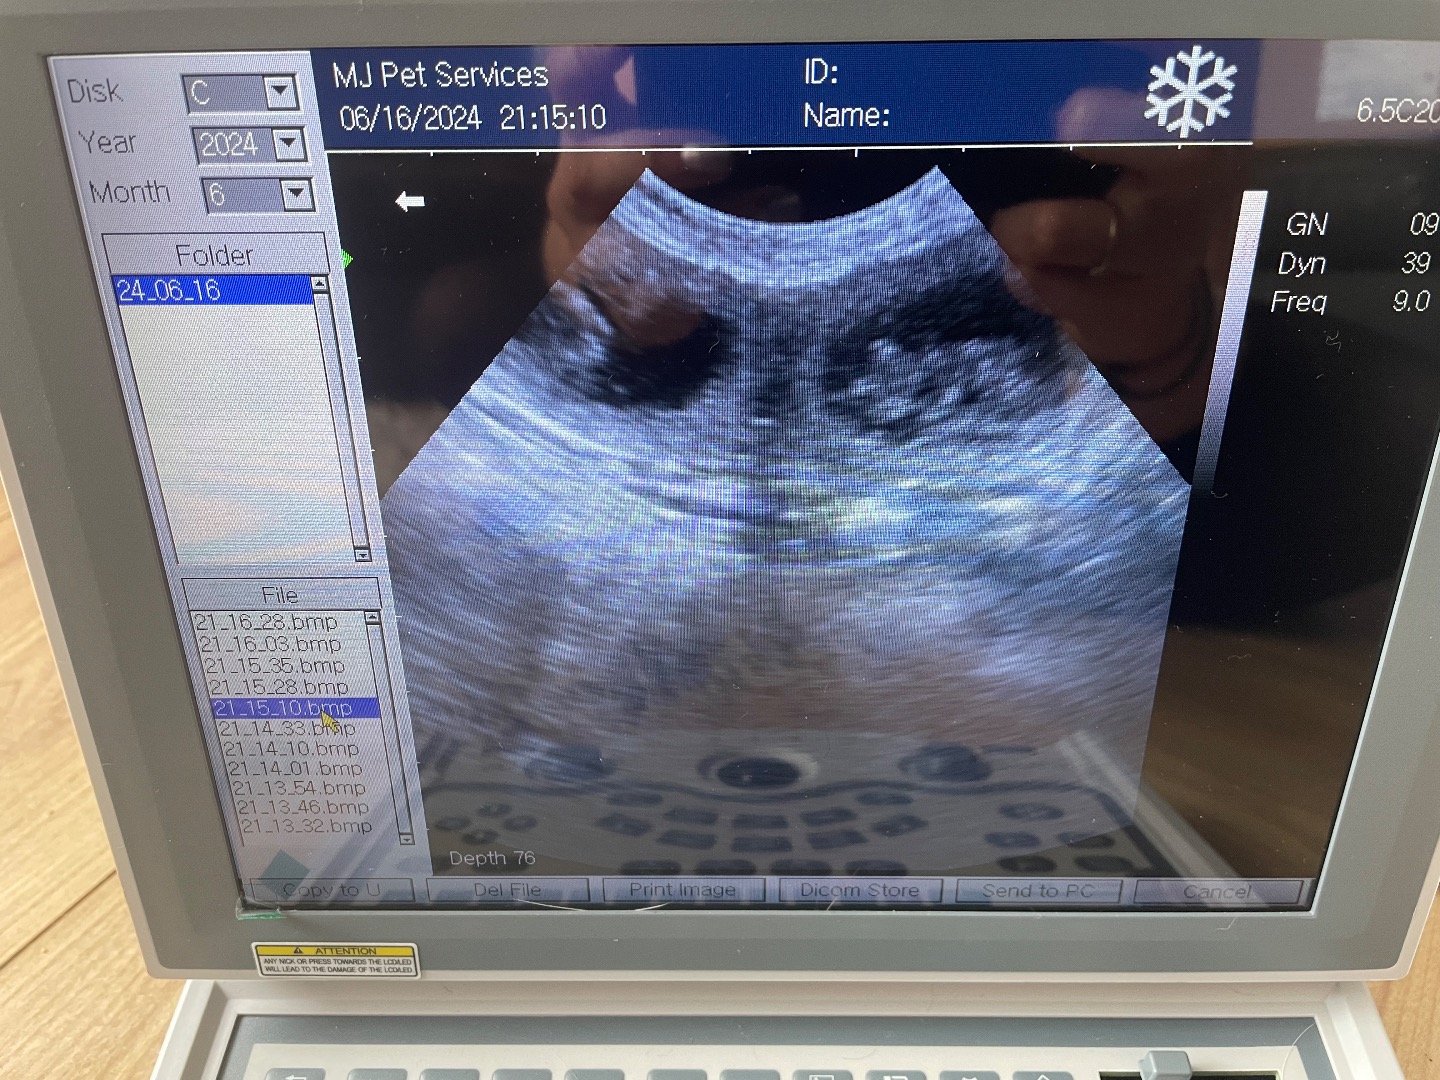

21 day confirmation scan of female Persian 4 year old first pregnancy.